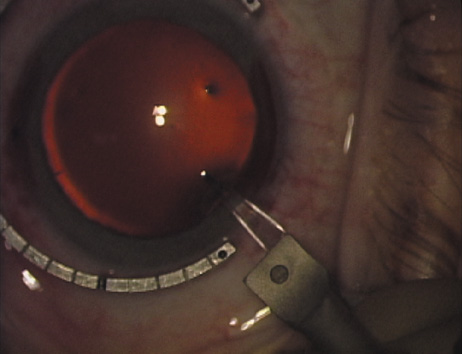

Case 1 is a 68-year-old male who presented for right cataract surgery. His refraction was −1.00 +2.25 × 80 and was recorded as reliable, consistent with his modest cataract density. Keratometry readings were 44.75 × 75 and 43.00 × 165. Corneal topography confirmed slightly more than 2.00 D of regular and slightly oblique cylinder. Consulting the nomogram, a plan was devised for a pair of LRIs to be centered over the 75-degree axis, with each incision delineating 45 degrees of arc. A single plane phaco incision was used and maintained at a size of less than 3.2 mm (Figs. 811).

Fig. 8. Steep meridian is confirmed intraoperatively by keratoscopy. In this left eye viewed from the temporal side, the “short axis” of the corneal mire is seen to be at the 75-degree meridian. (Reprinted from Hardten DR, Lindstrom RL, Davis EA. Phakic Intraocular Lenses: Principles and Practice. Thorofare, NJ: SLACK Incorporated, 2004, with permission.)